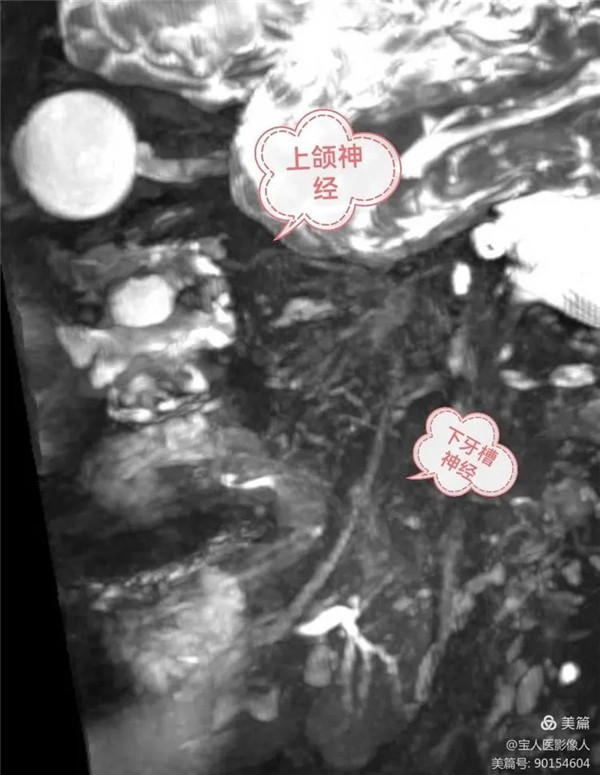

磁共振成像侧位图,同时显示上颌神经,下牙槽神经

上颌神经自三叉神经节发出后,立即进入海绵窦外侧壁,之后经圆孔出颅,进入翼腭窝,再经眶下裂入眶,续为眶下神经。上颌神经分支分布于上颌各牙、牙龈、上颌窦、鼻腔和口腔的粘膜以及睑裂间的面部皮肤以及部分硬脑膜。

(4) 下牙槽神经为混合神经,下牙槽神经在舌神经的后方,沿翼内肌的外侧面下行,一般躯体感觉纤维经下颌孔入下颌管。在下颌管内分支构成下牙丛,分支分布于下颌各牙和牙龈。